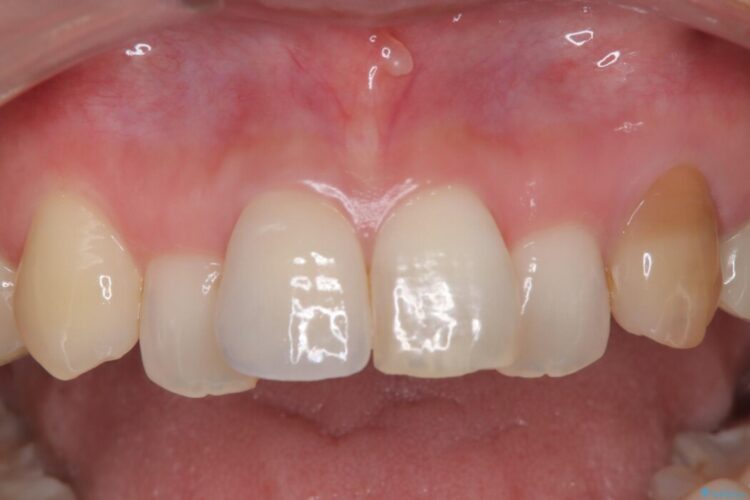

再根管治療とオールセラミックで前歯の気になる変色を解消

再根管治療とオールセラミックで前歯の気になる変色を解消 ビフォー 再根管治療とオールセラミックで前歯の気になる変色を解消 アフター

他院で神経を取った前歯が変色してきたとご相談にいらした患者様です。